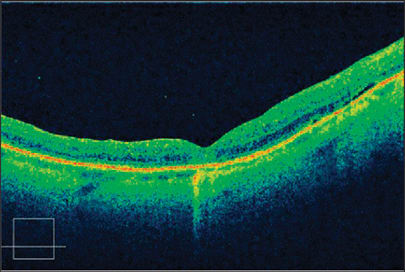

Figure 4. This is a high-resolution raster scan from Cirrus HD-OCT 1 week following successful macular hole surgery with ILM peeling. The patient received a 25% SF6 gas bubble injection and didn't require face-down posturing.